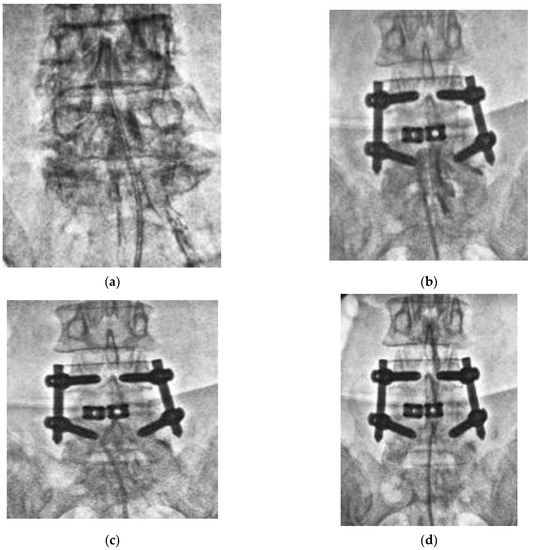

To date, there has been no comparative study investigating the efficacy of PEN between patients with and without FBSS. We named our lysis procedure TSCP and conducted a comparative study investigating the efficacy of TSCP between patients with and without FBSS in a multicenter analysis. Our results showed that TSCP significantly reduced low back pain and leg pain both in patients with and without FBSS. In this study, the majority of the patients were in their 60s to 80s. Before we could perform the TSCP procedure, we had to consider definitive surgery, even for the elderly patients, in case nonsurgical treatment failed. However, some of the elderly patients could not undergo general anesthesia due to their medical conditions. TSCP would be a less invasive approach for the elderly or immunocompromised patients under local anesthesia. However, leg pain significantly remained in FBSS patients 3 months and 6 months after TSCP. There might be a severe epidural adhesion in FBSS patients due to previous surgeries. The catheter was stuck, and contrast dye did not spread effectively at the site of adhesion (Figure 5b), and breakage of the tip of the catheter could occur (Figure 5c). Even when the contrast dye went into the cranial side, the distribution of dye seemed to be poor (Figure 5d); thus, the analgesic effect might be less in FBSS patients compared to patients without any history of lumbar spinal surgery (Figure 5a). There were three catheter breakages, and two of those cases were observed in FBSS, and one dural tear with transient neurological deficit occurred in FBSS patients. These complications might be related to severe adhesion in FBSS. Fortunately, there was no permanent neurological deficit or major complication perioperatively in this study. Marchesini et al. [19] reported that the complication rate of PEN was 8% in their review of 244 patients, and they found that more than half of complications were dural tears, and 93% of dural tears were observed in FBSS patients. Non-persistent post-procedural low back and/or leg discomfort/pain, transient neurological symptoms related to the increase in intracranial pressure, infection, post-procedural visual impairment with retinal hemorrhages, intravascular injection, encephalopathy resulting in rhabdomyolysis due to a dural tear, and neurogenic bladder and seizures were also reported as other perioperative complications. Avellanal et al. had proposed a “60 limit rule” for the prevention of an increase in intracranial pressure; procedures should not last more than 60 min, not exceed 60 mL of injection, and not exceed 60 mmHg of epidural pressure [20].

Figure 5. Epidurogram during TSCP procedure. (a) Epidurogram of a patient without any history of lumbar spinal surgery. The catheter was inserted into the epidural space with a mild to moderate resistance, and a spread of contrast dye seemed to be diffuse. (b) Epidurogram of a patient with a history of previous lumbar spinal surgery. The catheter was stuck, and contrast dye did not spread at the site of adhesion. (c) Breakage of tip of the catheter occurred due to severe adhesion in the epidural scape. (d) The distribution of contrast dye seemed to be poor.